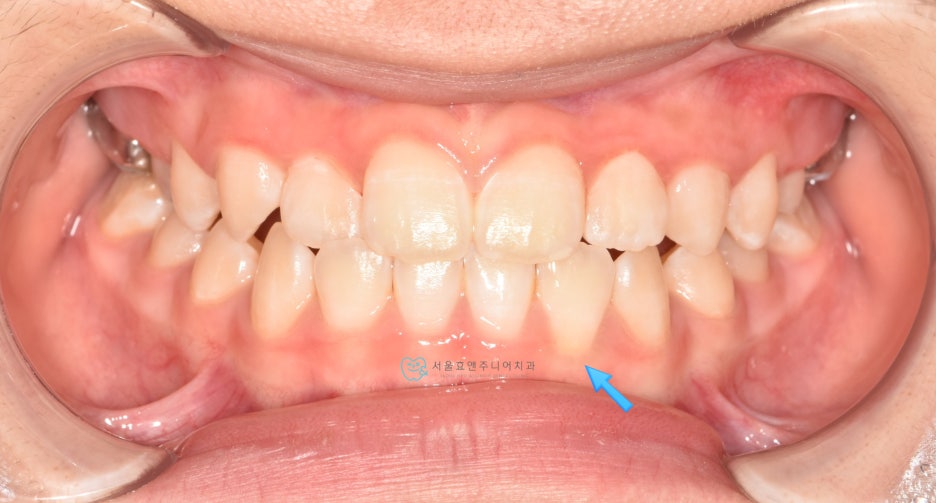

초진사진입니다

초진사진입니다. 11세 5개월 환아로, 반대교합을 보이고 있습니다. 반대교합으로 인해 치아가 부딪혀 치은퇴축(잇몸이 내려감)도 보이고 있네요.(화살표)